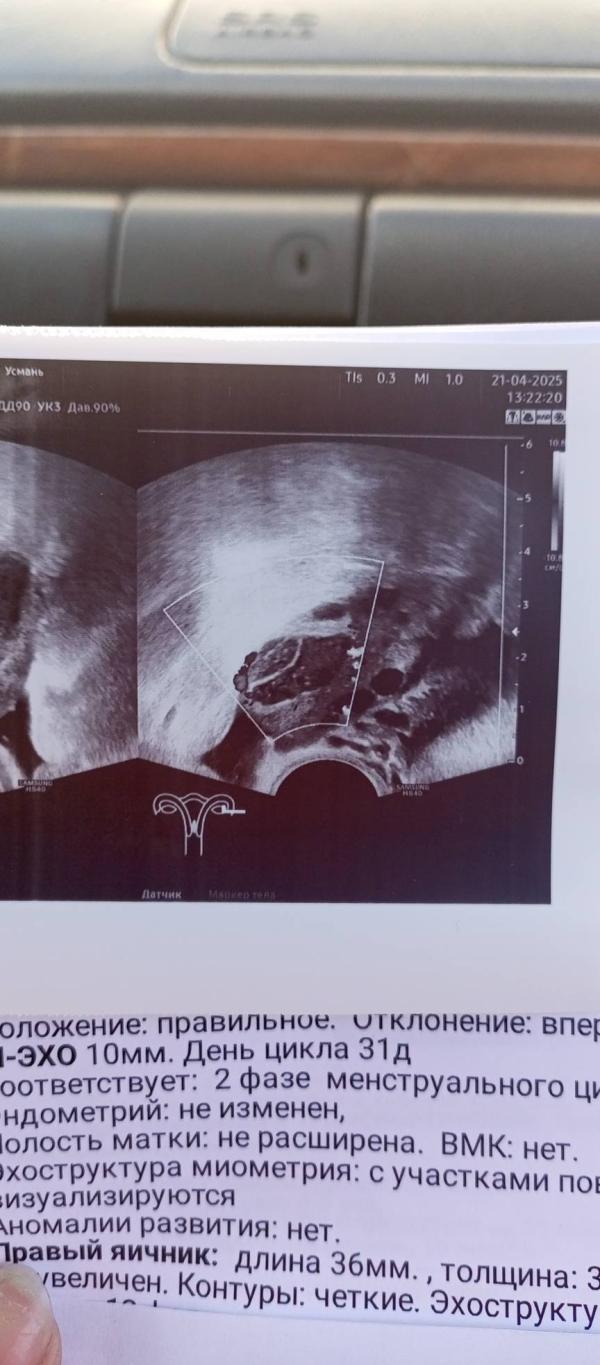

Здравствуйте, меня зовут Соня планирую беременность с августа 2022 года. Диагноз МФЯ, спкя под вопросом был, нерегулярный цикл редкая овуляция, раньше еë вообще не чувствовала. Пила Кок, дюфастон и тд, поменяла много врачей, а беременность так и не наступает( Много читала про Бады и назначала сама себе с них хоть как-то начало всё двигаться были бхб, мц вызывала Дюфастоном месячные пришли 22.03 закончились 26.03, где-то 8.04 начали ужастно болеть соски никогда такого не было потом появились выделения как ЯБ заказала тесты на овуляциюовуляцию, тесты стали ярчать с 10.04 пик по приложению стоит на 12.04 предположительно на 8дпо(вчера) я пошла в платную на узи и там было ЖТ 23*14, но беременности она сказала не видит, сказала делать тесты на б и смотреть появиться полоска или нет, если появиться подключить Дюфастон как поддержку, ещё я сдала хгч знаю что рано и он пришёл меньше 1.2,ещë рано расстраиваться, но моральго меня это убивает, простите если это слишком нудно, но так хочется выговориться... #первыйпост